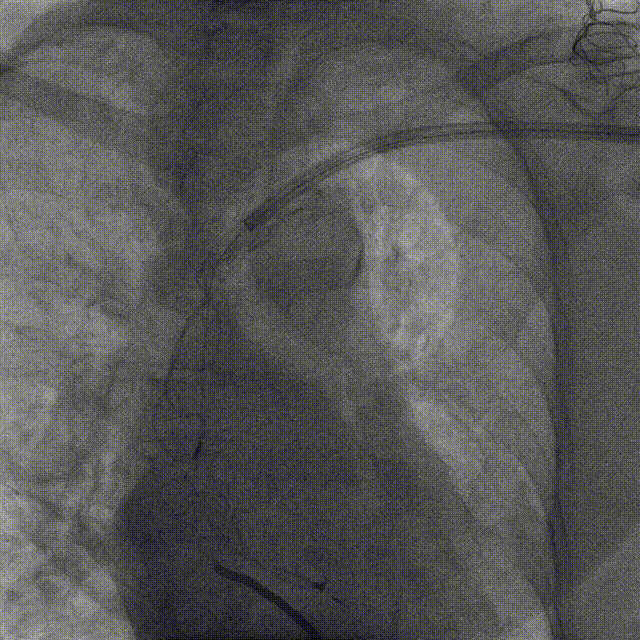

造影提示锁骨下静脉闭塞

手术中,潘小宏主任团队首先使用锁定导丝锁定除颤导线,随后使用 11F 机械扩张鞘沿除颤导线分离粘连组织,顺利拔除位于右心室除颤电极导线。